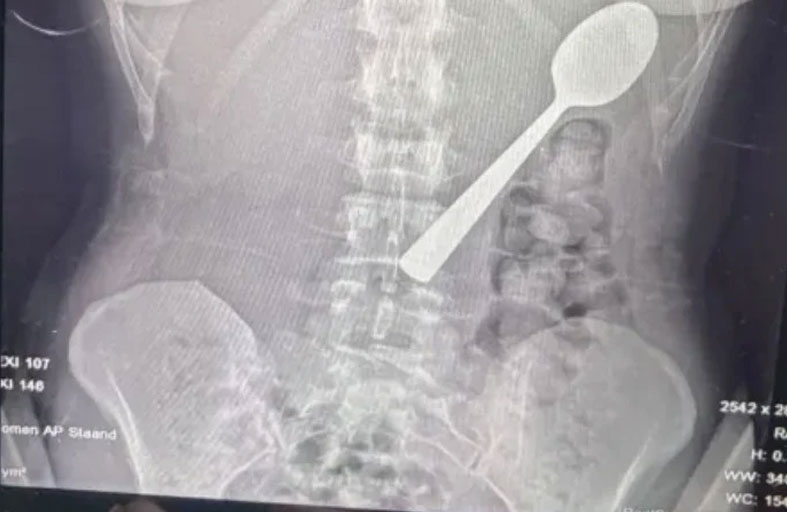

تعرضت امرأة بلجيكية لموقف صادم بعدما ابتلعت ملعقة بطول 17 سنتيمتراً عن طريق الخطأ أثناء تناولها الطعام، وذلك بعد أن قفز كلبها على جسدها بشكل مفاجئ.

وقالت ريمي أملينكس، البالغة من العمر 28 عاماً، إنها اضطرت للاختيار بين الاختناق أو ابتلاع الملعقة، مشيرة إلى شعورها بأنها "انزلقت بسلاسة إلى معدتها".

وبعد تناول العشاء، أدركت خطورة الموقف، وذهبت إلى الأطباء الذين أبلغوها أن الملعقة كبيرة جداً لتخرج طبيعياً، ما استدعى انتظار إجراء منظار معدة.

وأُزيلت الملعقة بعد يومين تحت التخدير الموضعي، حيث اضطر الأطباء لتدويرها داخل المعدة، ما تسبب في نزيف بسيط، وأكدت ريمي أن الحادث لم يترك أي أضرار دائمة، لكنها تعرضت لالتهاب في الحلق ونزيف في المعدة طفيف وحساسية لبعض الوقت.